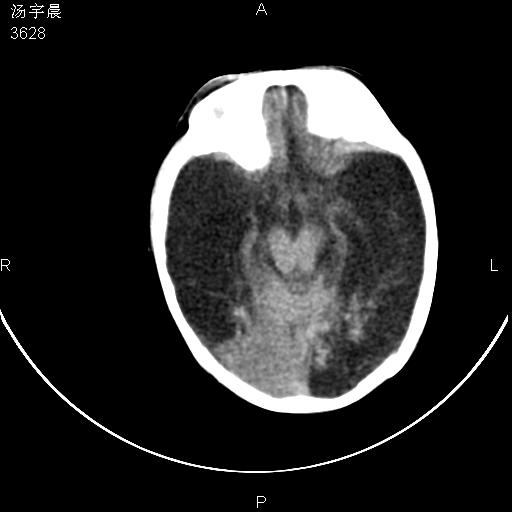

早产儿,现两月大,2月份在某医院诊断病毒性脑炎并治疗,mri报右颞部脑白质片状长t2信号,脑白质模糊。其他不详,现家属要求ct复查 。

双侧大脑半球大片状低密度,无明显占位表现, 符合病毒性脑炎。

小儿病毒性脑炎ct表现缺乏特异性,但其定位分布有一定特异性,单纯疱疹病毒性脑炎ct表现以颢叶病变为主,同时可累及其他脑区或伴出血,乙型脑炎表现为基底及丘脑的病变,流行性腮腺病毒性脑炎则ct表现可正常,故ct检查对病毒性脑炎的定性有重要的价值。 本例支持:病毒性脑炎的后遗改变!